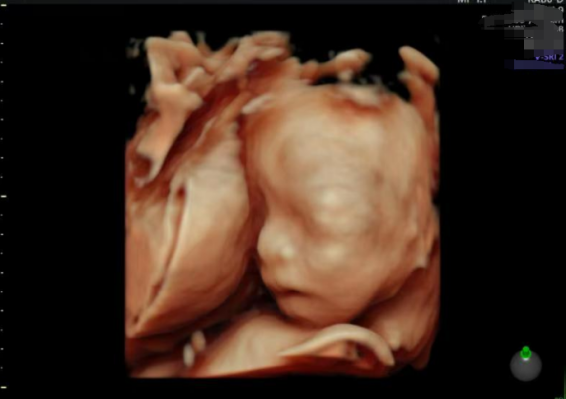

特别难忘的是胚胎从零下196度的液氮中解冻及移植当日,机构发来的解冻图片——那颗标记4AA的女宝囊胚在培养液中舒展后,透明带如花瓣般绽开着。等看到代妈移植B超影像里那个闪烁的小光点,突然理解到生命传承的神奇。这个承载着我先生和台湾女孩基因密码的胚胎,将在泸沽湖妇女的子宫里,与摩梭人特有的基因共存九个月。现代医学创造的这种生命联结,远比血缘更令人敬畏。

(我的代妈转换黄体前的检查)

Ø 契约母亲腹中的心跳

大约孕7周左右收到B超报告,看到“胎心搏动”,无比激动。后来做四维大排畸彩超显示:三尖瓣口见少量反向血流信号,机构转达产科医生的解释:“这是胎儿心脏发育中的常见现象”,果然复查心脏彩超显示的反流消失,印证了医生关于“发育性生理现象”的判断,悬着的心终于放下了。

(移植后的第一次B超)

(四维B超大排畸)